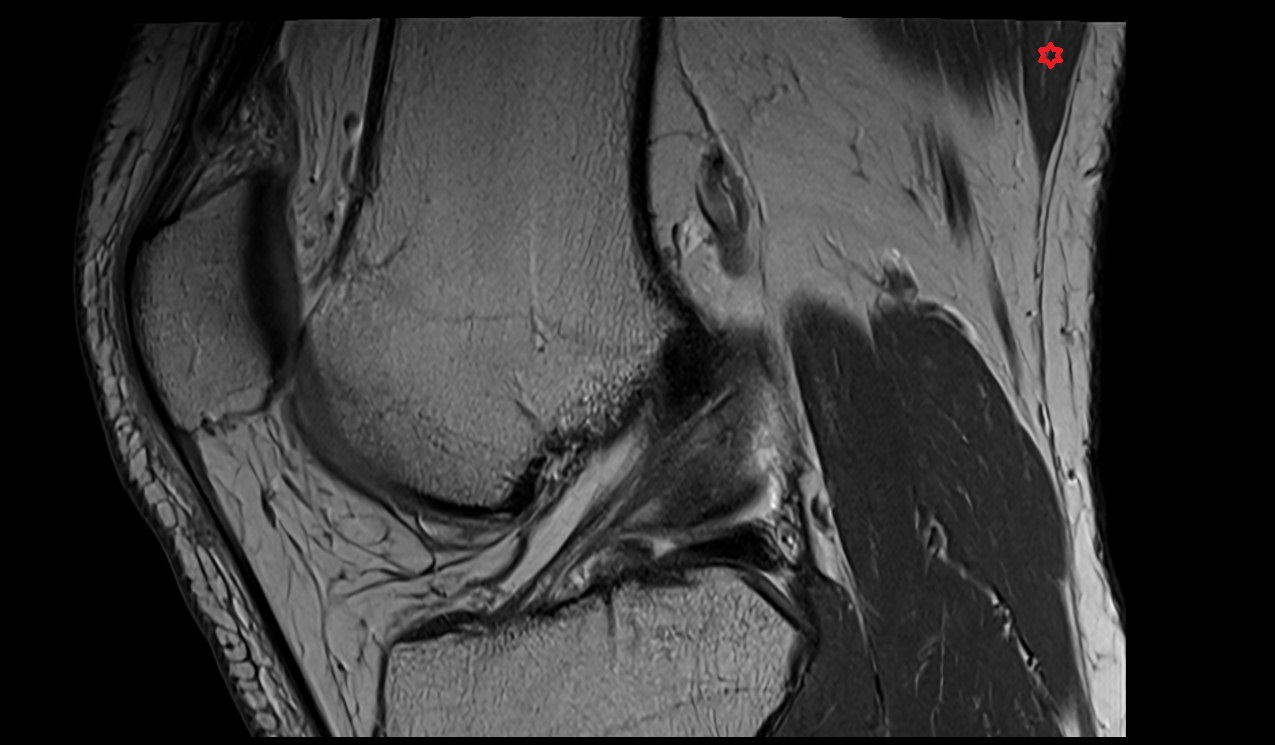

- Anterior cruciate ligament

- Posterior cruciate ligament

- Medial meniscus

- Lateral meniscus

- Lateral condyle of femur

- Medial condyle of femur

- Femoral condyle articular cartilage

- Tibial condyle articular cartilage

- Patella

- Patellar articular cartilage

- Infrapatellar fat pad

- Knee Joint